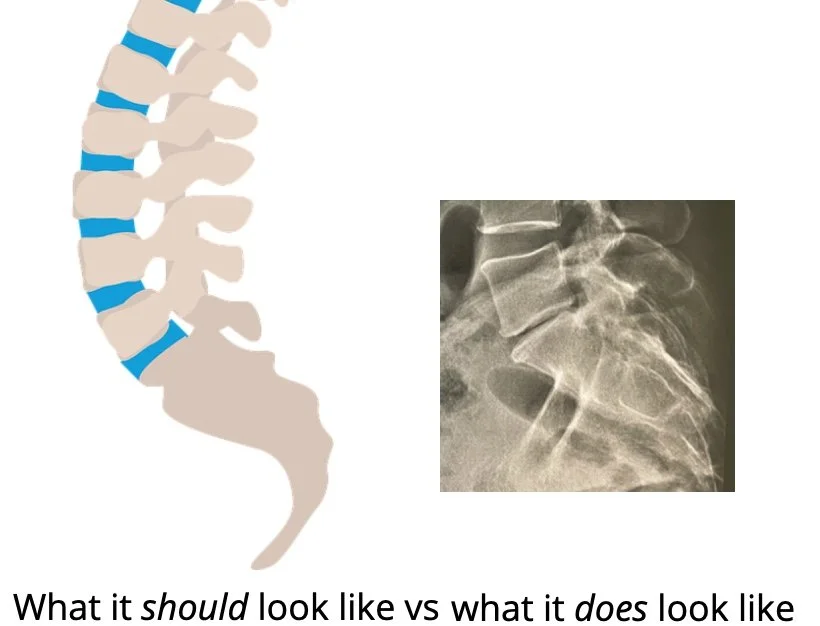

<p></p>]]></description><item><title>The Road to Recovery</title><category>injury</category><dc:creator>Nathalie Descusse-Brown</dc:creator><pubDate>Sat, 04 Nov 2023 15:30:01 +0000</pubDate><link>https://www.rungineer.com/blog-1/2023/10/16/the-road-to-recovery</link><guid isPermaLink="false">5a9288481137a6fdeeb6e5ab:5ae04633758d461f5dbc4003:652d4fa206564c109d2f691b</guid><description><![CDATA[<p class="">I didn’t blog in 2022. I had started my <a href="https://www.rungineer.com/blog-1/2022/4/26/how-i-got-my-boston-unicorn-">Boston Marathon post</a> after running it last year, and only finally published earlier this month. Work got in the way. But something else happened too in August last year, that threw a spanner in the work: I got injured. After the Boston marathon and a result I was happy with, I had reflected on the fact that I had barely done any strengthening exercises as part of my marathon training and somehow managed to run the entire marathon with no injury besides pretty bad chaffing and a lost toe nail. I need to clarify that not including strengthening in my training schedule was not intentional. Well, I could and definitely should have done it, but trying to juggle studying, marathon training and mothering was tough and anything that wasn’t strictly one of those just didn’t get done. I didn’t think much of it and really took my fitness for granted. Until August 2022. </p><p class="">My parents were keen skiers. Our annual ski holiday was the highlight of the year for me. It beat our summer beach camping trips even though it was much shorter. I started taking alpine ski lessons when I was 4. My dad loved downhill skiing too, but it was not my mums’s cup of tea and she would always leave us to it and go nordic skiing. One day I decided to swap my alpine skis for nordic skis and go with my mum. The feeling was very odd: not only my foot was not fully attached to the ski but the skis also felt so light. I was careful, did a little bit of flat and then when I had gained confidence I went for a very gentle downhill slope (so gentle it was almost flat). But I fell right on my coccyx. It was painful for a while after that and I vouched to never do any nordic skiing again (although I’m starting to consider again now, 30 years later). Ever since I have had some pain in my coccyx if I remain seated for too long (that became more obvious as I started work and had extended periods in front of the computer or equally long times seating in meetings). But that never prevented me from doing any sport, and I never really gave it a second thought. Until August 2022.</p><p class="">August 2022 is when I started noticing pain in my lower back. I was awkwardly moving some boxes in the packed garage looking for something and felt some pain but it’s happened before and I didn’t think much of it at first as it appeared to go away as quickly as it started.  But over the next few months the pain kept visiting me on and off and gradually got worse. So I turned to my GP, who referred me to get an X-Ray. This is when I discovered I had degenerative disc disease. The X-ray couldn’t have been clearer: I had pretty much no disc left between two of my vertebrae (the one between L5 and S1 for those of you in the know!). At first I panicked: would that be the end of running for me? So I researched it and asked my coach who provided some helpful advice and reassured me. But soon the pain in my lower back got worse and my movements were getting more and more restricted. I was struggling to put socks on and do my laces. But at that point running was not painful so I kept at it.</p>